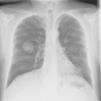

A continuación, se presenta de un varón de 49 años, sin antecedentes personales de interés, fumador (80 cigarrillos/día) y con un hábito enólico importante (60g/día). Consultó de urgencia por una cianosis de aparición súbita en los 3 primeros dedos de la mano izquierda, precedido de palidez cutánea, acompañado de parestesias y dolor intenso (fig. 1). No presentaba otra sintomatología indicativa de enfermedad sistémica y la exploración física era por lo demás normal. La auscultación cardiaca era rítmica y sin soplos, y los pulsos distales estaban presentes y eran simétricos en todas las extremidades. El estudio de coagulación fue normal, salvo el dímero-D, que fue mayor de 5.000ng/ml, con un tiempo de cefalina y protrombina normales. Se realizó un eco-Doppler arterial que evidenció presencia de vascularización hasta la región interdigital de todos los dedos de la mano afectada. La arteriografía puso de manifiesto una oclusión distal de la arteria radial del segundo dedo, con oclusión proximal de las arterias digitales palmares de los dedos segundo y tercero. La radiografía de tórax objetivó una masa de 4 cm en el lóbulo inferior derecho (fig. 2), cuya punción-aspiración con aguja fina fue compatible con un carcinoma de pulmón de células gigantes. El estudio de extensión no evidenció afectación ganglionar. El tratamiento inicialmente pautado fue heparina de bajo peso molecular, con mejoría leve de la sintomatología cutánea. Por ello se añadió de forma secuencial pentoxifilina, ácido acetil-salicílico y alprostadilo por vía intravenosa con resultados discretos. Tras la resección tumoral, presentó una evidente mejoría clínica, con resolución del fenómeno de Raynaud.